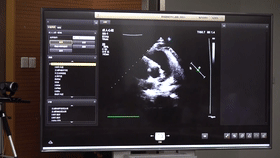

5G遠(yuǎn)程會診現(xiàn)場,西安國際醫(yī)學(xué)中心心內(nèi)科張衛(wèi)澤主任、超聲科陳姍姍主任打開4K高清顯示器,屏幕上立刻出現(xiàn)了商洛國際醫(yī)學(xué)中心的B超畫面,一位醫(yī)生正在為患者做心臟B超,隨著探頭的轉(zhuǎn)動,超聲機(jī)器上的畫面清晰可見,雖然兩家醫(yī)院相距一百多公里,但畫面流暢,沒一點(diǎn)拖沓。

“真的太棒了”張衛(wèi)澤表示,“沒有延時與卡頓,清晰的好像在一個房間內(nèi)進(jìn)行病歷討論”。陳姍姍非常興奮,直呼很震撼。她告訴筆者,“以前做遠(yuǎn)程會診,經(jīng)常遇到畫面和聲音不在一個頻道、畫面模糊等情況,遇到疑難病歷只能將影像拷下來回去研究,現(xiàn)在好了這些問題都將一次性解決?!?/span>